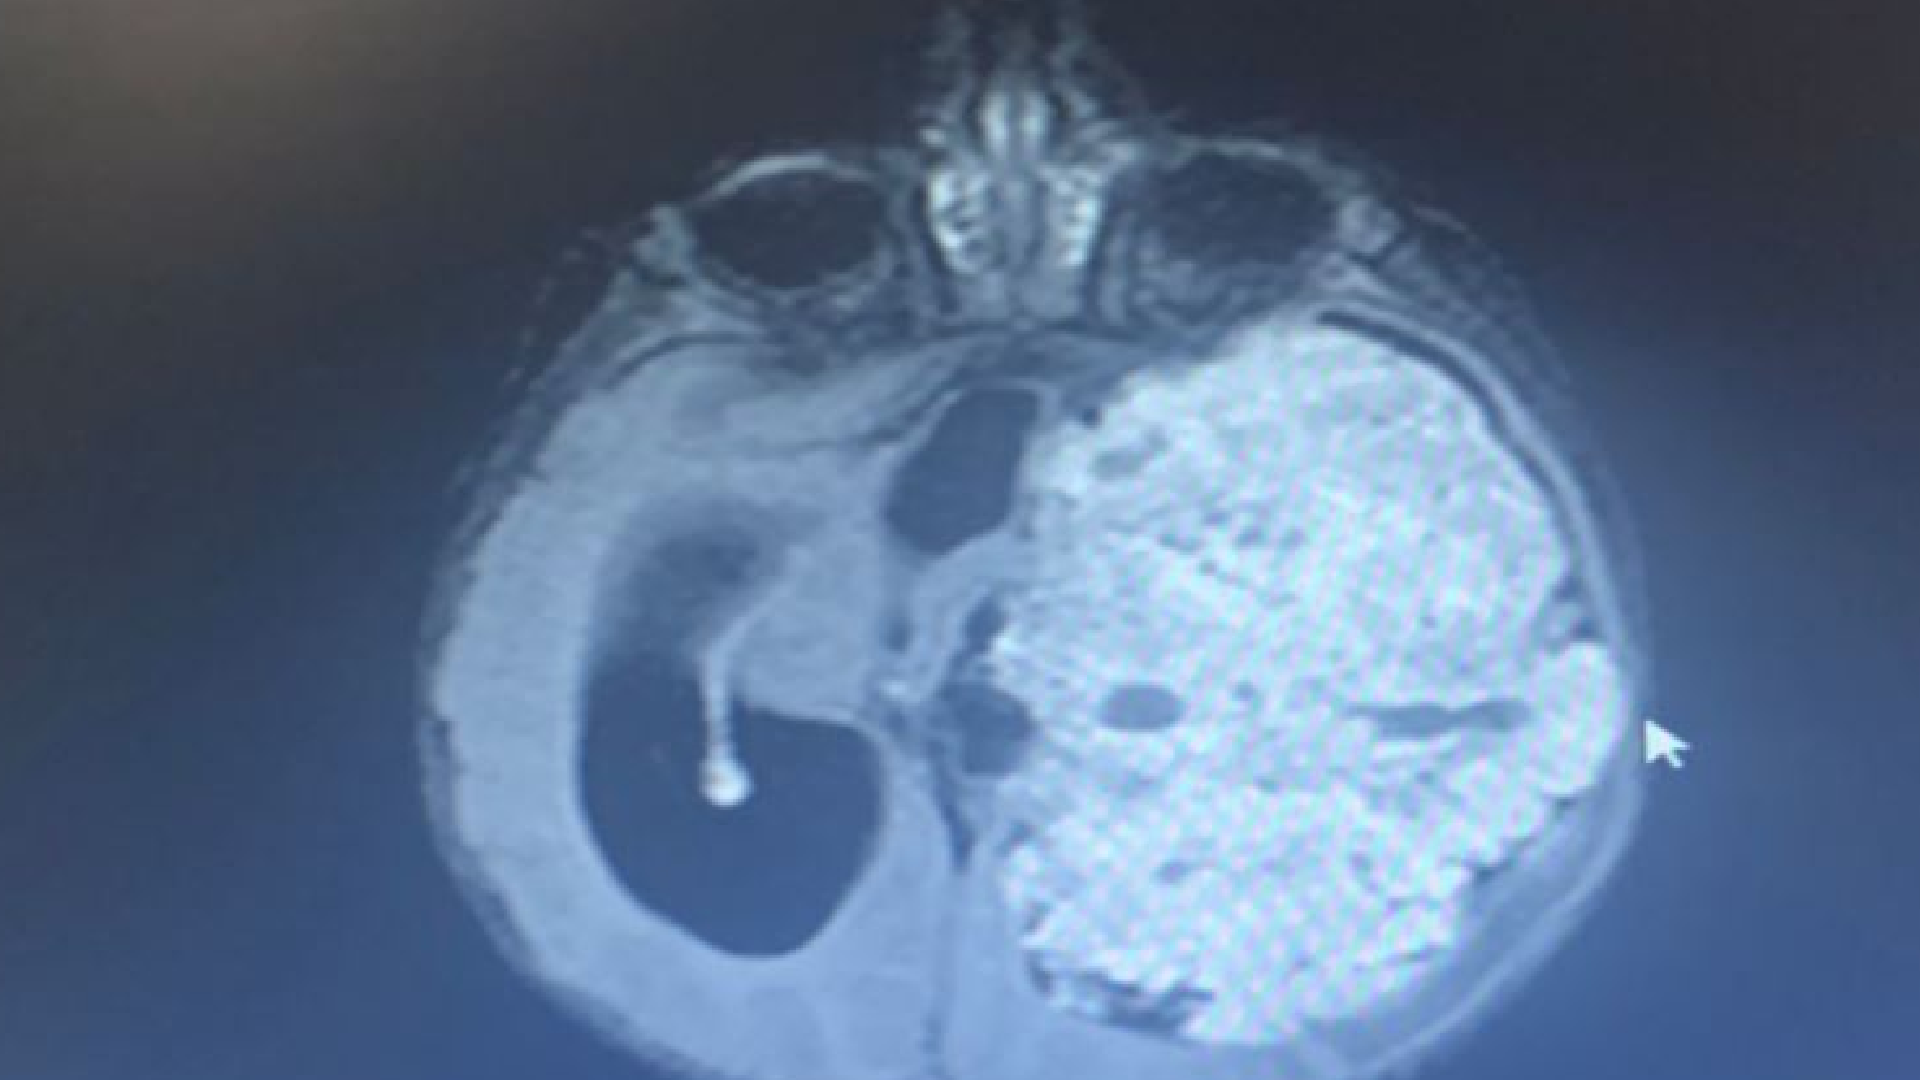

Şanlıurfa'da 1,5 yıllık evli Saniye ve Yunus Kılıç, 3 aylık bebekleri Mehmet Asaf Kılıç'ın kafasının sol tarafında oluşan şişliği fark edince Şanlıurfa Eğitim ve Araştırma Hastanesi’ne başvurdu. Beyninde kitle olduğu belirlenen Asaf bebek, Ankara Sağlık Bilimleri Üniversitesi Gülhane Eğitim ve Araştırma Hastanesi’ne sevk edildi. Asaf'ın çekilen MR'ında beynin sol tarafının tamamen tümör ile kaplı olduğu tespit edildi. Asaf bebeğin ameliyat edilmesi kararlaştırıldı ve 9 saat süren operasyonla beynindeki tümör temizlendi. Asaf bebek, tedavi sürecinin ardından sağlığına kavuştu.

Mehmet Asaf'ın doktoru Beyin ve Sinir Cerrahisi Uzmanı Doç. Dr. Cahit Kural, Asaf'ı ilk gördüklerinde yolunda gitmeyen bir şeyler olduğunu hissetiklerini belirterek, "Acil olarak MR çektirdik. Beyin MR'ında beynin sol tarafını tamamen dolduran, sağ tarafına bası yapan devasa bir kitle vardı. Zaman kaybetmeden hemen ameliyata aldık. Ameliyatta tümörün tamamını çıkardık. Bu büyüklükte tümörler çok nadir görülür. Beynin yarısını dolduran bir tümördü. Hastamız çok küçük, tümör çok büyük, riskli bir ameliyattı. 8-9 saat süren bir ameliyatın ardından iyileşti, sağlıklı şekilde evine gönderiyoruz" dedi.

Çıkarılan örnekleri ileri inceleme için patoloji bölümüne gönderdiklerini belirten Kural, "'Atipik koroid pleksus papillomu' tanısı geldi. Bu çok nadir görülen bir tümör. Beyni bu kadar dolduran tümör görmek, çoğu zaman mümkün değil. Tümörün hepsini çıkardığımız için kemoterapi düşünmüyoruz" diye konuştu.